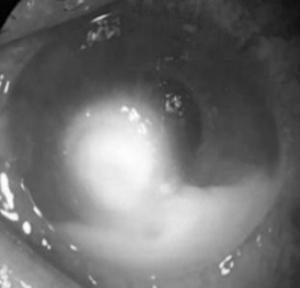

De este total, 10 (40%) recibieron QP de urgencia, todos ellos de sexo masculino con un promedio de edad de 38 años. En las figuras 2 y 3 se observa un caso antes y después de la cirugía.

Figura 2. Absceso corneal por Fusarium spp. Caso de un paciente previo a la cirugía.